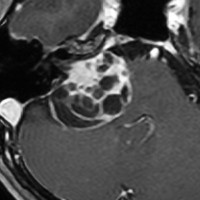

大きなのう胞性聴神経腫瘍です。いくつかの袋が重なって腫瘍を形成しています。橋や延髄(脳幹部)が変形して,第4脳室がつぶれて閉塞しています。袋の周りが白く線状に造影されているのですが,この袋の壁だけに腫瘍細胞がありますから,これを剥がすように摘出します。顔面神経が薄くなって袋の壁にくっついているのですが,袋を破ってくしゃくしゃにすると顔面神経の位置が変わってしまって,顔面神経を損傷することがあるので要注意です。のう胞性聴神経腫瘍の方が顔面神経麻痺の後遺症の頻度が高いという報告もあるくらいです。この患者さんは迷走神経と舌咽神経の圧迫も強くて,ご飯を飲み込むことが難しくなっていました(嚥下障害)。